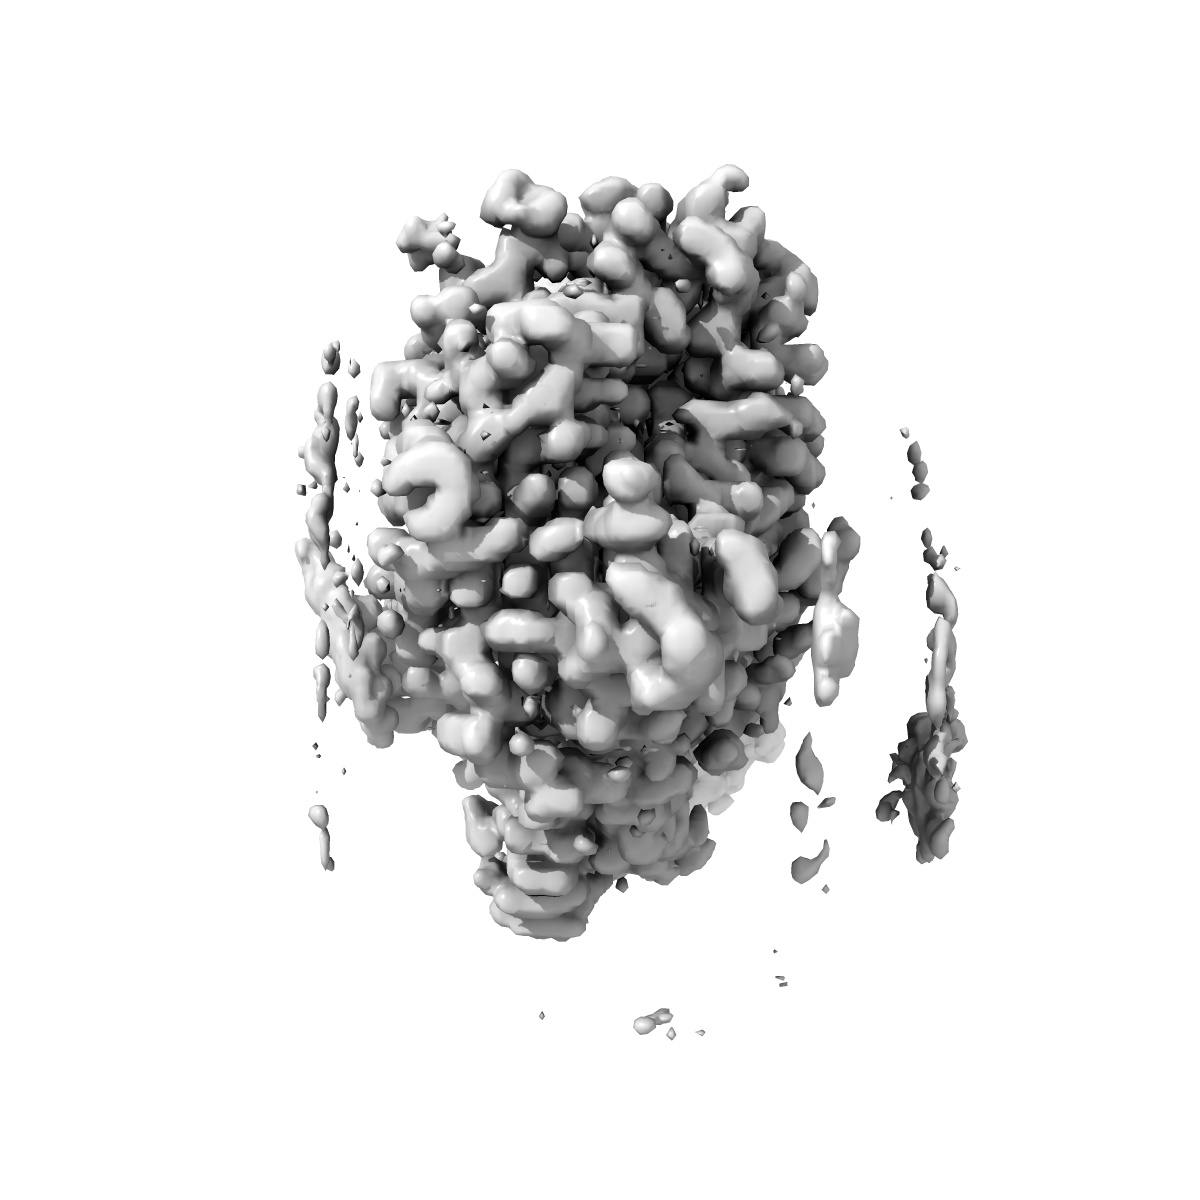

This entry was superseded by EMD-70618.Cryo-EM structure of the C. neoformans lipid flippase Apt1-Cdc50 bound with butyrolactol A in the E2P state

Single-particle2.72 Å